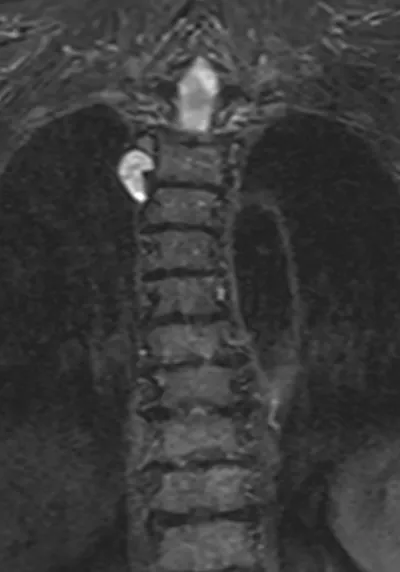

Paraspinal Mass Radiology Images

This collection contains 1 radiology images related to paraspinal mass, including various imaging modalities such as X-rays, MRIs, CT scans, and ultrasound images commonly used in medical diagnosis and education.